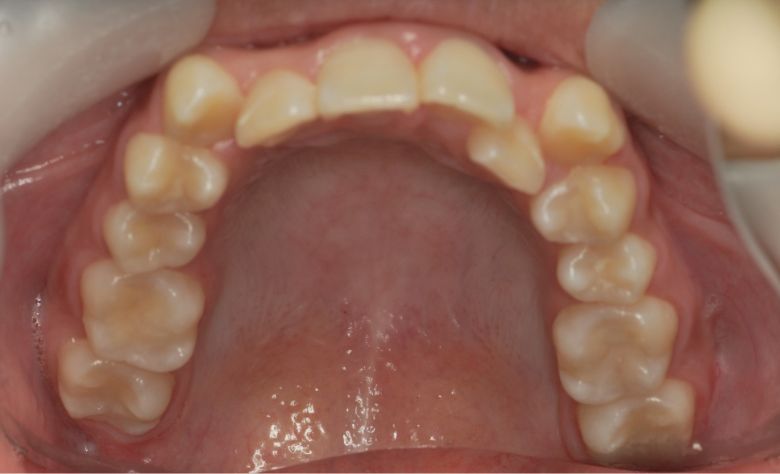

上下顎ともに犬歯が唇側に大きく突出しており、歯列弓が狭小なため、

他院では上下左右4本の便宜抜歯を前提とした矯正治療を提案されていました。

上顎には左右の犬歯が著しく唇側に偏位している

精密検査の結果、当院では抜歯を行わず、歯列弓の拡大によってスペースを確保し、非抜歯での矯正治療を選択しました。歯列の叢生(ガタガタ)は解消され、機能的かつ審美的に優れた咬合が得られました。